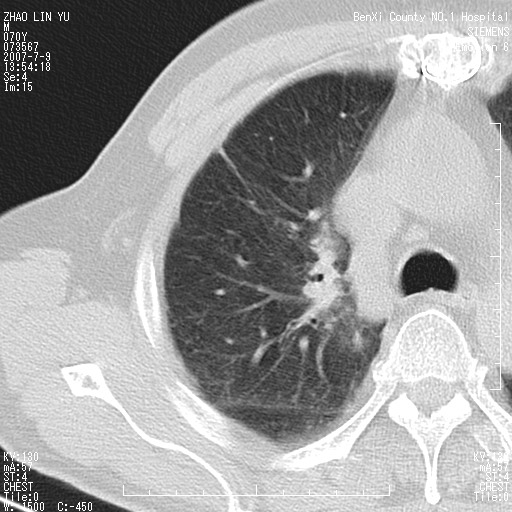

以下是引用王靖旗在2007-7-10 17:12:00的发言:[br] 男、70、咳嗽两个月,半年前换瓣手术,胸片未见异常,于昨天行x片发现右肺上野大片影,行ct扫描,这里是减薄图像,余肺正常。明天晚上会有增强扫描片,到时我会上传。[br][br] 冠状位请大家细看,应该是有意义的,[br][br] 请大家先看平扫发表意见。[br][br]

以下是引用zhangzhongshou在2007-7-10 21:43:00的发言:[br]右肺上叶周围型肺癌,以孤立型细支气管肺泡癌可能性大。